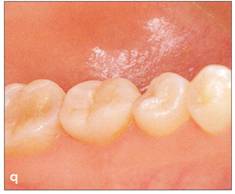

Fi 545e45f g 5.1q Occlusal relationship after transplantation. The donor tooth is out of occlusion. Fi 545e45f g 5-1r Protection of the wound and prevention of infection by the use of surgical dressing. |

Fi 545e45f g 5-15 Three weeks after transplantation. Root canal therapy was started 2 weeks after transplantation. After temporary obturation with calcium hydroxide, the root canal was obturated with gutta percha in 5 weeks. Fi 545e45f g 5-1t Two and one half months after transplantation. |

Fi 545e45f g 5-1 u Definitive occlusal restoration of the donor tooth with composite resin. Fi 545e45f g 5-1v One year 3 months after transplantation. Normal periodontal ligament space and lamina dura are observed. |